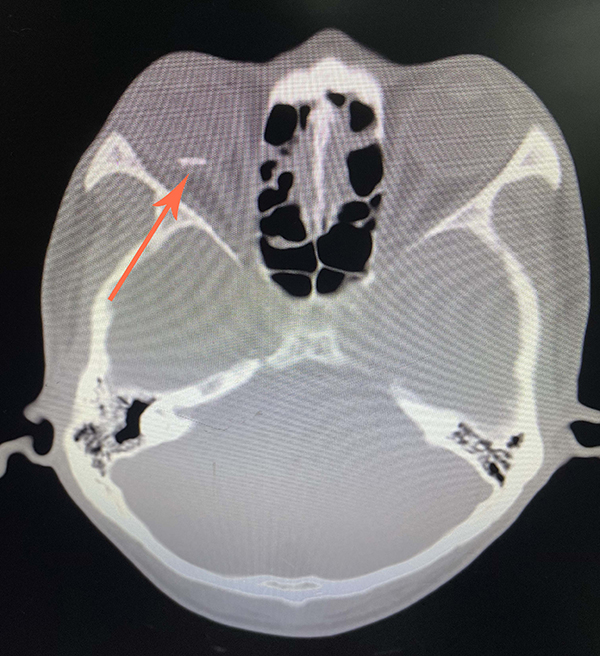

楊先生意識(shí)到,有東西飛進(jìn)了他的眼睛。他連夜到當(dāng)?shù)蒯t(yī)院就診。醫(yī)生給他做了裂隙燈和眼眶CT等檢查,發(fā)現(xiàn)他的眼球內(nèi)有一個(gè)異物,診斷其為右眼球穿通傷并球內(nèi)異物、右眼外傷性白內(nèi)障。

做入院檢查時(shí),醫(yī)生發(fā)現(xiàn)楊先生只能看見眼前的手在晃動(dòng),至于幾根手指在動(dòng),他看不清。此外,楊先生的角膜有一道長約7毫米的全層破裂口,晶狀體全變白了,眼底視網(wǎng)膜的情況完全看不見。